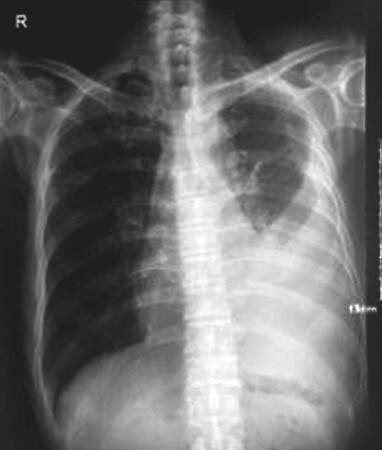

入院查体:形体消瘦,左肺叩诊呈浊音,听诊左肺呼吸音低。胸部彩超示:左侧胸腔大量积液(图1)。于入院后第2日行胸腔穿刺并细管引流术,当日共引流出约800ml血性浑浊液体。两次胸腔积液送细胞学:见癌细胞(腺型)。免疫组化:细胞角蛋白7(CK7)癌细胞(+)。血清肿瘤标志物(血还是胸腔积液?):细胞角质素19片段3.37ng/ml,糖类抗原72-4 9.03U/ml。引流3日后胸腔积液量<150ml/d,第4天引流袋内突发气泡溢出,呼吸困难加重,即刻行胸部CT示:左侧液气胸(引流术后),左肺部分萎陷、左侧胸膜增厚(图2)。该患者穿刺过程顺利,术后3日内,呼吸困难症状无反复,胸腔引流袋内未见气体逸出,第4天引流袋内突发气泡溢出,呼吸困难加重,提示穿刺操作失误造成气胸发生的可能性较小,而胸膜肿瘤灶脱落,形成癌性气胸的可能性较大。

图1 胸部X线片显示左侧胸腔大量积液